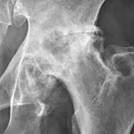

Note: (1) the progressive roughening of the round ball and its socket,

(2) the decreasing clear space (cartilage and fluid) between them,

(3) and the extra rough bone (white material) around the joint.

https://commons.wikimedia.org/wiki/File:Severe_(T%C3%B6nnis_grade_3)_osteoarthritis_of_the_hip.jpg

Description English: Projectional radiography of the left hip of

a 65 year old man with pain upon hip movement. It

shows severe (Tönnis grade 3) osteoarthritis.

Description English:

Projectional radiography of the left hip of a 65 year old man with pain

upon hip movement. It shows severe (Tönnis grade 3)

osteoarthritis.